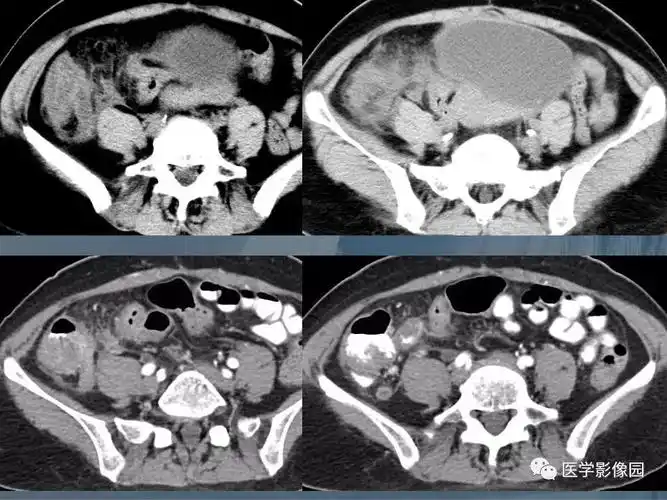

阑尾炎的ct诊断